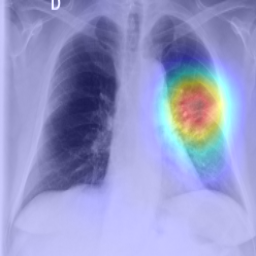

We used four publicly available CXR collections in our evaluation of the proposed approach. These collections are the Radiological Society of North America (RSNA) shih2019augmenting, the Shenzhen TB Jaeger et al. (2014), the Montgomery TB Jaeger et al. (2014), and the Pediatric pneumonia dataset Kermany et al. (2018).

The RSNA dataset includes 26,684 normal and abnormal frontal CXRs that are provided as DICOM images with spatial resolution. In addition to the labels, GT disease bounding boxes are made available for CXRs containing pneumonia-related opacities. The Shenzhen dataset contains 662 CXR images (336 abnormal and 326 normal image-level labels) and GT binary masks for the lungs (pixel-level labels). The size of the images in this collection varies, but it is approximately pixels. The Montgomery dataset has 138 posterior-anterior CXRs of which 80 CXRs are normal and 58 are abnormal with TB manifestations. The images have pixel resolution. The abnormal class for Montgomery dataset includes a wide range of abnormalities, including tuberculosis-related manifestations, effusions, and miliary patterns. Finally, the Pediatric pneumonia dataset was collected from 624 patients and labeled as described in Kermany et al. (2018). The train set contains a total of 5,232 chest X-ray images, including 3,883 labeled as pneumonia (2,538 bacterial and 1,345 viral) and 1,349 labeled as normal. The test set contains 234 normal images and 390 pneumonia images (242 bacterial and 148 viral). Figure 2 shows labeled image examples from the aforementioned CXR datasets.